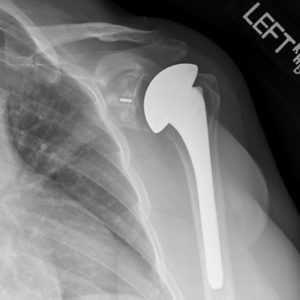

Рентген после эндопротезирования плечевого сустава

Если ранее человеку стоило больших трудов и страданий, к примеру, завести руку за голову или спину, отвести ее в сторону, поднять вверх или удержать даже самый легковесный предмет, то после установки эндопротеза обо всех этих трудностях реально забыть. Однако произвести исключительно замену сочленения недостаточно, пациенту необходимо после нее упорно работать над своим восстановлением, чтобы однозначно получить отличный положительный эффект от пройденного хирургического мероприятия.

Шрам после реверсивного эндопротезирования плечевого сустава

Максимальному возвращению двигательного потенциала способствует реабилитация после эндопротезирования плечевого сустава, которой отведена не менее значимая роль, чем самой операции. Только пройдя качественно весь путь послеоперационной реабилитации, человек может рассчитывать на благоприятный прогноз - восстановление функциональности прооперированного отдела на 95 %-100 %. Конечно, при условии, что и протезирование было выполнено без изъянов - на высшем профессиональном уровне.